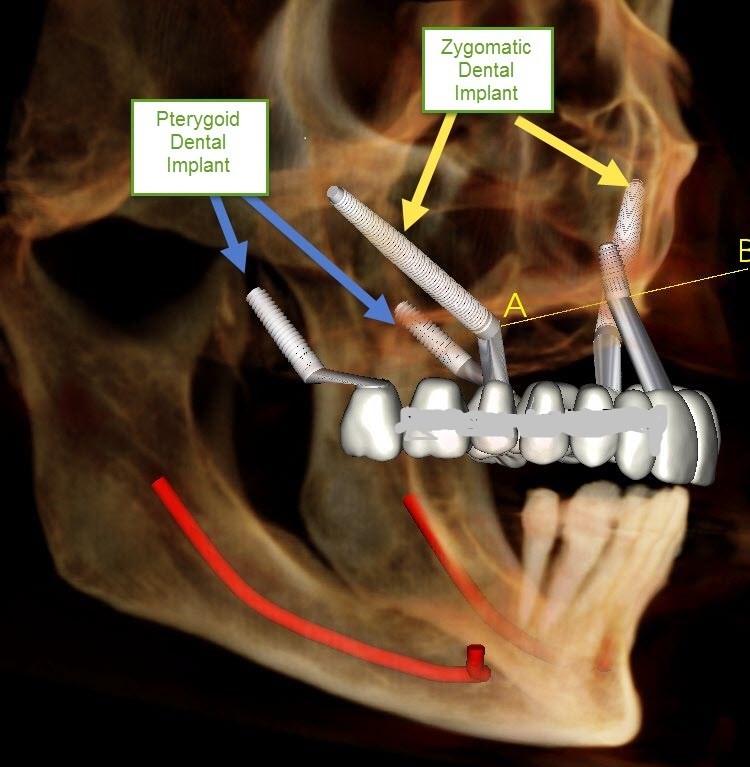

Zygomatic Implants

Zygomatic implants are specialized dental implants designed for patients with severe upper jawbone loss who may not be suitable for conventional implants. Instead of being placed in the jawbone, these implants are anchored into the strong cheekbone (zygoma) to provide maximum stability and support for full-mouth teeth replacement. Zygomatic implants often eliminate the need for extensive bone grafting procedures and offer faster smile restoration with long-lasting results. This advanced treatment improves chewing ability, facial appearance, speech, and confidence while providing a secure and permanent solution for complex dental implant cases.

Pterygoid Implants

Pterygoid implants are advanced dental implants placed in the back portion of the upper jaw to support fixed teeth in patients with severe bone loss. These implants are anchored into the strong pterygoid bone, providing excellent stability without the need for sinus lift or extensive bone grafting procedures. Pterygoid implants are commonly used in full-mouth rehabilitation treatments and help restore missing teeth with improved strength, comfort, and function. This advanced implant solution offers faster treatment, long-lasting support, natural-looking results, and enhanced chewing ability for patients seeking a permanent smile restoration option.